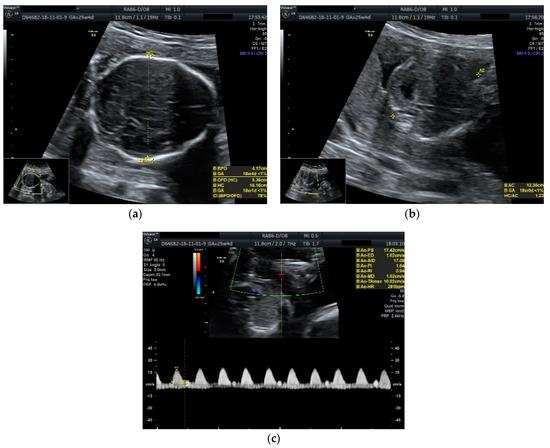

Obstetric ultrasonography showed a diamniotic dichorionic twin pregnancy, both fetuses alive, with discordant growth. Measurements for the first fetus were appropriate for 25 weeks and 4 days of gestation with normal amniotic fluid volume, whereas the biometry for the second one revealed much lower dimensions corresponding to 18 weeks and 4 days of gestation with low amniotic fluid volume. No fetal anomalies were seen. A Doppler scan showed increased pulsatility and resistivity indices in the umbilical artery for the growth restricted fetus (PI: 1.64, RI: 0.94, absent diastolic flow and sinusoidal pattern of the venous umbilical flow) (Figure 1).

Figure 1.

Ultrasound scan performed at 25 weeks and 4 days of gestation: (a) biparietal diameter of the growth restricted fetus appropriate for 18 weeks and 4 days of gestation; (b) abdominal circumference of the growth restricted fetus appropriate for 18 weeks and 0 days of gestation; (c) umbilical artery Doppler scan of the growth restricted fetus showing the absence of diastolic flow.